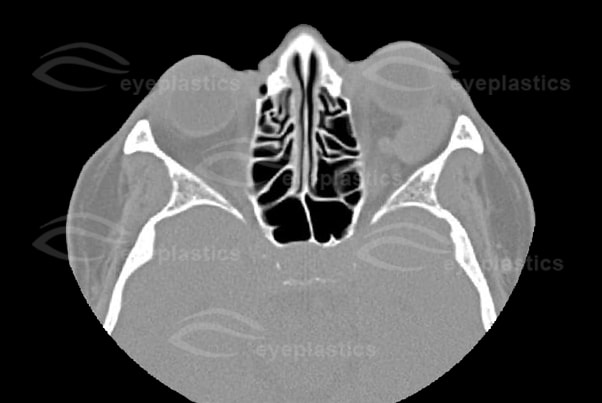

- CT scan detects an oval or round, homogenous mass with sharp margins, but falls short of a definitive diagnosis.

Imaging of Cavernous Hemangioma

- CT: smooth discrete lesion, fills with dye after 20 min; coronal cuts important to know tumor position relative to optic nerve. for sugical plan

- MRI: hypointense to fat on T1, hyperintense to fat on T2